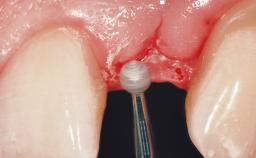

Late Placement of an Implant in a Maxillary Left Central Incisor Site

On examination, the patient had a low lip line and only displayed the coronal half of the anterior teeth when smiling.

The crown of tooth 21 was splinted to the adjacent teeth with composite resin, and the gingiva was inflamed.